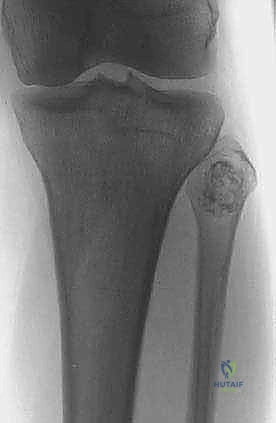

* أورام الخلايا العملاقة (Giant Cell Tumors): شائعة في نهايات العظام الطويلة وتميل للعودة إذا لم يتم استئصالها بالكامل.

* الأكياس العظمية المتمددة (Aneurysmal Bone Cysts).

- الأشعة السينية (X-rays): الخطوة الأولى. تظهر التغيرات في الهيكل العظمي، تآكل العظم، أو التفاعلات السمحاقية (Periosteal reaction) التي تدل على وجود ورم.

- التصوير المقطعي المحوسب (CT Scan): ممتاز لتقييم التفاصيل الدقيقة للقشرة العظمية واكتشاف أي تكلسات داخل الورم.